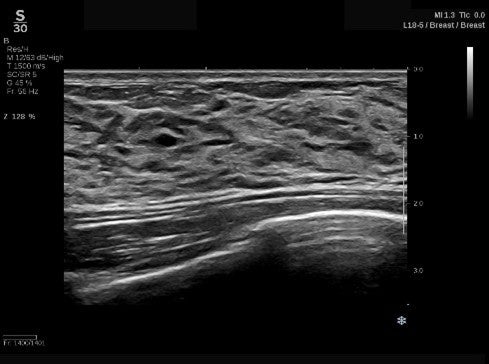

(2)進化したSWE PLUS™イメージング

従来システムではSWEのレンジは800 kPaまででしたが、SUPERSONIC™ MACHシリーズでは、最大1200 kPaまで測定が可能*となっています。

*MSKプリセット使用時

整形領域では腱や筋肉の硬さ、乳腺領域では腫瘍の硬さ、肝臓領域では、肝組織の硬さを評価することで、疾患の早期診断に貢献します。